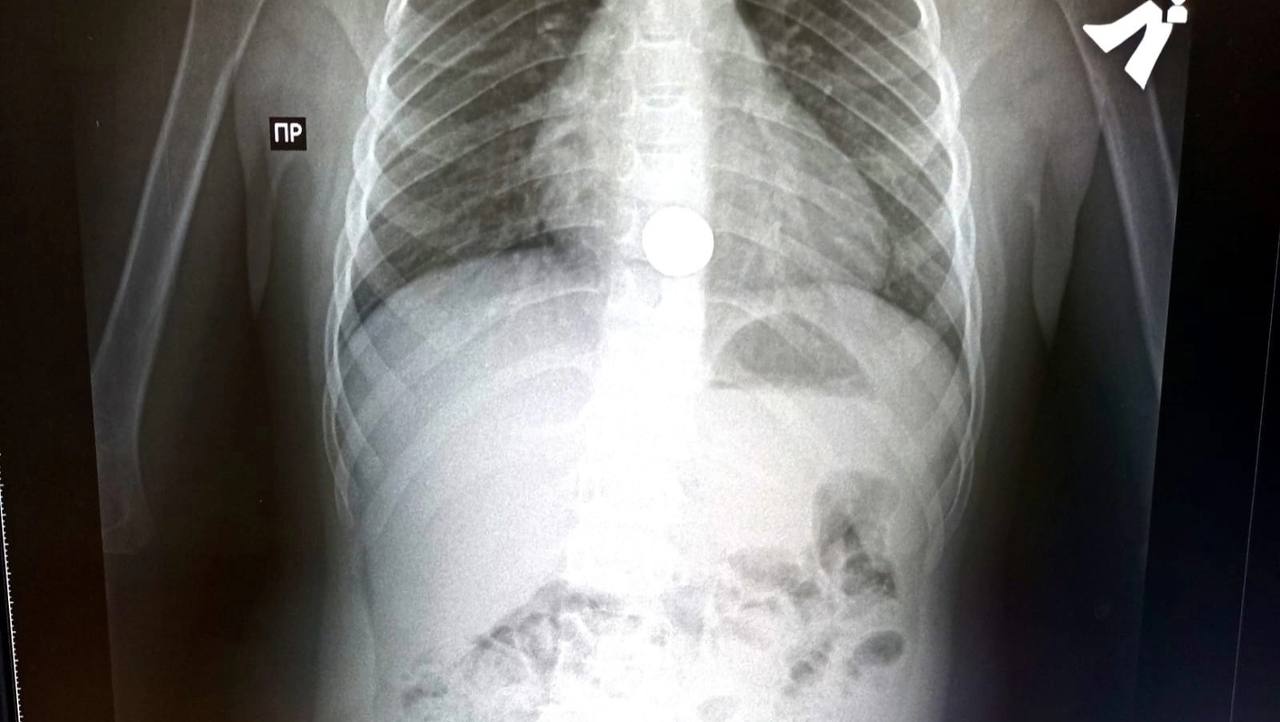

В Башкирии проглотившему монету ребенку потребовалась экстренная медпомощь

В детскую больницу Салавата поступил 5-летний ребенок. Играя монетами, одну из них он проглотил. Родители сразу же отвезли его в больницу, где под общим обезболиванием было произведено эндоскопическое удаление монеты